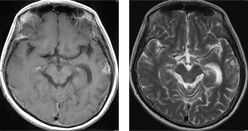

症例 2

卵巣癌による右前頭葉を中心に多発転移性脳腫瘍に対して放射線治療単独(全脳照射)のみで腫瘍が著明に縮小しました。その後再発なく経過しています。